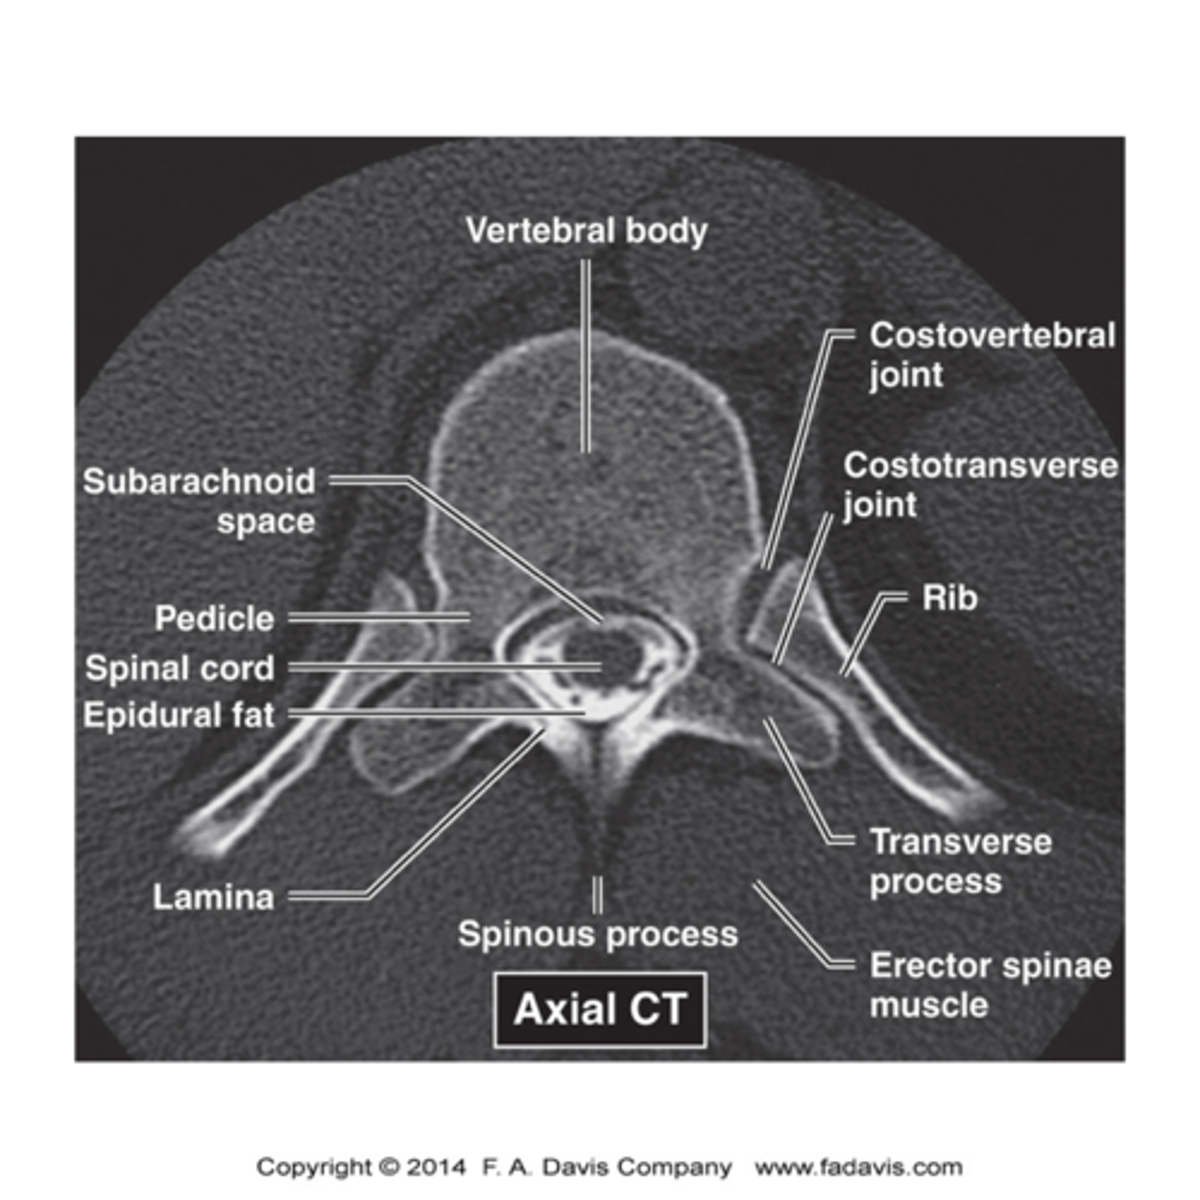

spine imaging

MRI- study of choice for spinal cord, intervertebral discs, compression of spinal nerves

CT- best for bony abnormalities, MRI contraindicated, non contrast for trauma